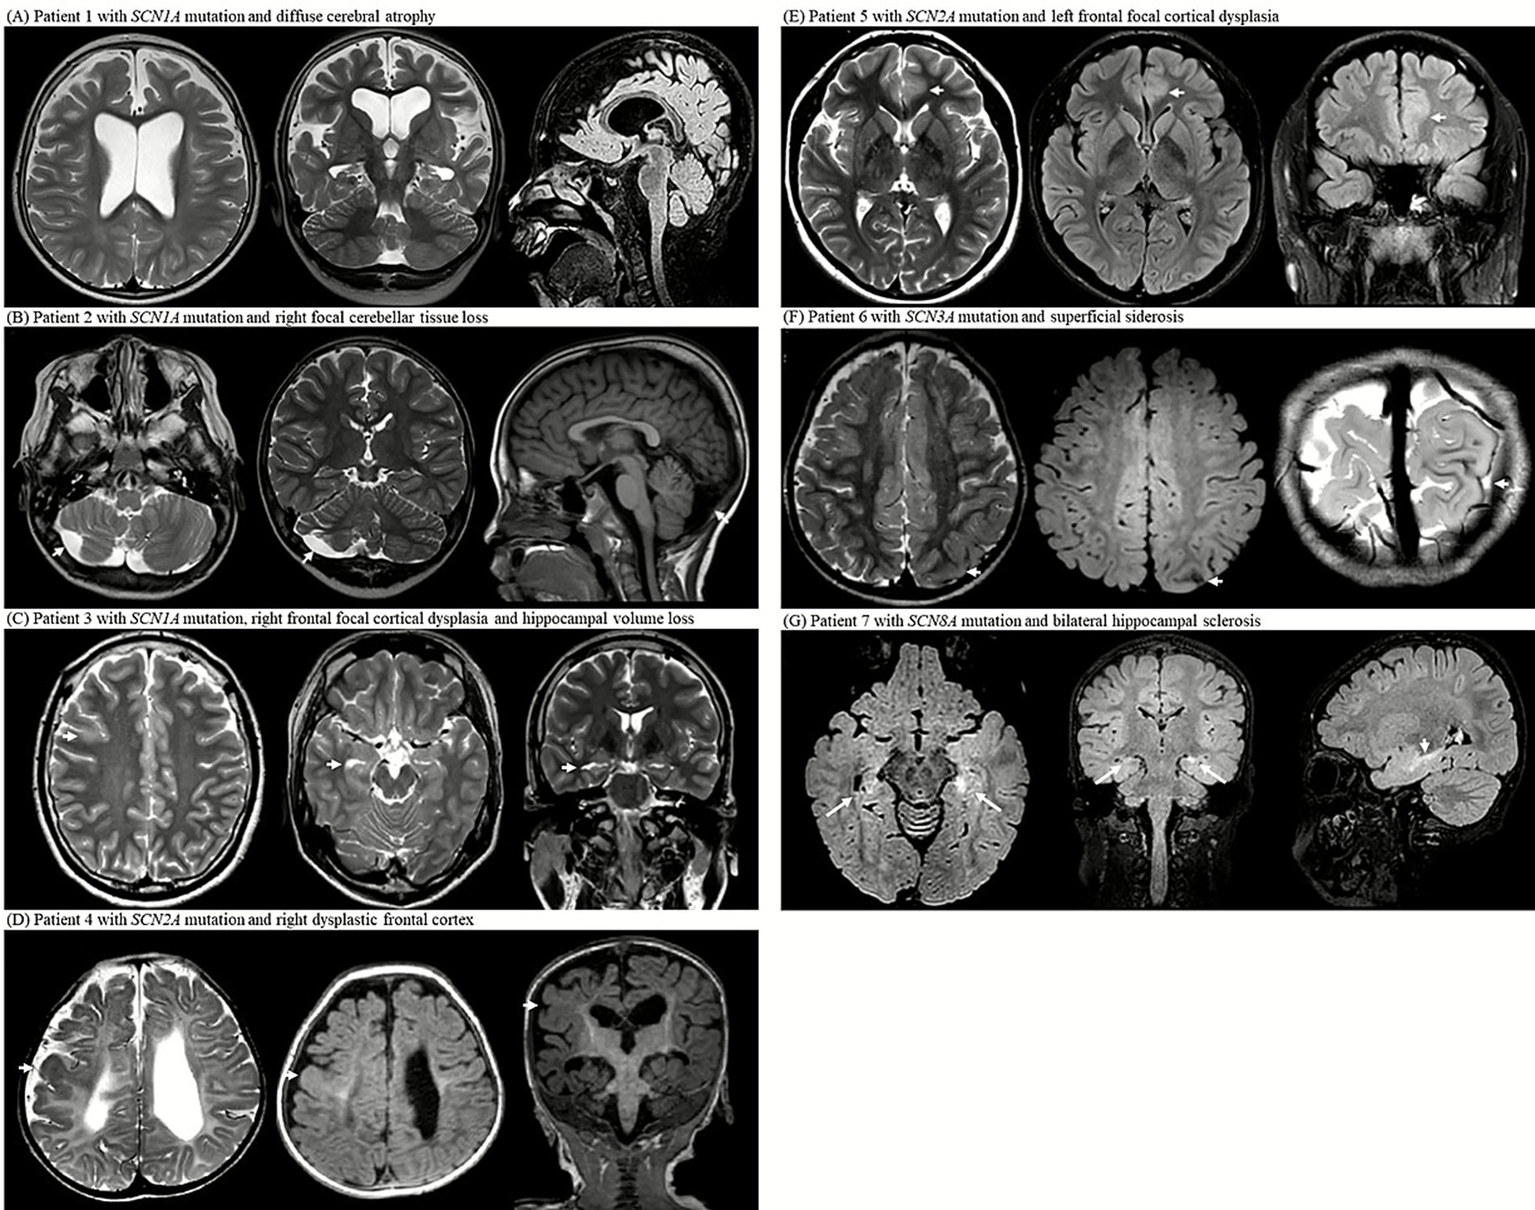

Patient 1: An 8-year-old boy with a heterozygous SCN1A missense mutation (c.680T>G; pIle227Ser) presented with febrile and hemiclonic seizures starting at 4 months of age, including prolonged status epilepticus. Seizures improved significantly (>90% reduction) after cannabidiol was introduced at the age of 4 years, alongside a ketogenic diet. MRI at the age of 6 years revealed diffuse cerebral atrophy and bilateral ventriculomegaly. Earlier developmental assessment at the age of 3 years indicated a profound global delay (Figure 2A).

Figure 2

MRI examinations from seven patients with SCN gene mutations (SCN1A, SCN2A, SCN3A, and SCN8A) reveal a spectrum of structural abnormalities. (A) Axial T2-weighted image at the level of the lateral ventricles, coronal T2-weighted image showing the hippocampal formation, and sagittal midline FLAIR image of patient 1 with SCN1A mutation; the images demonstrate diffuse cerebral atrophy with marked bilateral ventricular enlargement. (B) Axial T2-weighted image at the level of the cerebellum, coronal T2- weighted image through the cerebellar hemispheres, and sagittal midline T1-weighted image of patient 2 with SCN1A mutation; the images show focal right cerebellar tissue loss with mild asymmetry. (C) Axial T2-weighted image at the centrum semiovale, axial T2-weighted image at the midbrain level, and coronal T2-weighted image showing the hippocampus of patient 3 with SCN1A mutation; the images reveal right frontal focal cortical dysplasia and ipsilateral hippocampal volume loss. (D) Axial T2-weighted image at the level of the lateral ventricular atrium, axial FLAIR image at the same level, and coronal T1-weighted image of patient 4 with SCN2A mutation; the images demonstrate diffuse periventricular leukomalacia with thinning of the corpus callosum and dysplastic cortex of the right frontal lobe. (E) Axial T2-weighted image at the level of lateral ventricles, axial FLAIR image at the same level, and coronal FLAIR-weighted image of patient 5 with SCN2A mutation; the images show focal cortical thickening and subcortical white matter T2 high signal intensity in left anterior cingulate gyrus, consistent with focal cortical dysplasia. (F) Axial T2-weighted image at the centrum semiovale, axial FLAIR image at the same level, and oblique coronal T2-weighted image at the occipital lobe level of patient 6 with SCN3A mutation; the images show superficial siderosis along the left parietal convexity. (G) Axial FLAIR image at the midbrain level, coronal FLAIR image at the foramen of Monro level, and sagittal midline FLAIR image of patient 7 with SCN8A mutation; the images show bilateral hippocampal atrophy with increased T2/FLAIR signal intensity and loss of internal architecture, consistent with hippocampal sclerosis.

Patient 2: A 23-year-old man with an SCN1A insertion mutation (c.1875_1876insG; p.Ser626GlufsTer2) had seizure onset at five months. Despite polytherapy with antiseizure medications, seizures persisted. MRI at the age of 6 years revealed right cerebellar tissue loss (Figure 2B).

Patient 3: A 21-year-old male with a heterozygous SCN1A nonsense mutation (c.1141C>T; p.Gln381Ter) developed focal motor seizures with status epilepticus at 14 months of age. Despite multiple antiseizure medications and a ketogenic diet, the seizures persisted and worsened upon stiripentol discontinuation. MRI at 19 years of age revealed a dysplastic cortex in the right frontal area and right hippocampal volume loss (Figure 2C).

Patient 4: A 6-year-old girl with a heterozygous SCN2A missense mutation (c.4499C>T; p.Ala1500Val) had refractory neonatal-onset epilepsy with bilateral clonic seizures beginning 10 min after birth, evolving into daily myoclonic seizures. MRI at 6 months showed diffuse white matter volume loss and corpus callosum thinning with a dysplastic cortex in the right hemisphere. Electroencephalogram (EEG) confirmed the presence of sharp focal waves. Despite extensive treatment with antiseizure medications, seizures remained intractable. She exhibited profound developmental delays, hypotonia with dystonic posturing, and feeding difficulties requiring gastrostomy. By the age of 2 years, the EEG showed diffuse slow spike-and-wave discharges and paroxysmal fast activity, consistent with Lennox–Gastaut syndrome (Figure 2D).

Patient 5: A 20-year-old female with a heterozygous SCN2A splice-site mutation (c.3400-2A>G) experienced nocturnal hypermotor seizures at the age of 3 years. MRI at the age of 15 years showed focal cortical thickening and subcortical T2 hyperintensity in the left cingulate gyrus, suggestive of focal cortical dysplasia. EEG confirmed the presence of frontal focal sharp waves. The seizures were well controlled with medication, and development remained normal (Figure 2E).

The single SCN3A patient exhibited superficial siderosis in the left parietal lobe, likely a sequela of a prior subarachnoid hemorrhage (Table 2).

Patient 6: An 8-year-old boy with a heterozygous SCN3A splice-site mutation (c.3393+2T>G) developed infantile epileptic spasms at 13 months of age and daily atonic seizures with regression. Despite treatment with multiple antiseizure medications, the seizures were drug-resistant. MRI at 18 months of age revealed superficial siderosis of the left parietal lobe. Developmental testing at the age of 3 years showed a global delay (Figure 2F).

In the SCN8A group, 3/7 (42.9%) patients had MRI abnormalities. Atrophy was observed in 2/7 (28.6%) patients, white matter signal abnormalities (T2 hyperintensities) in 1/7 (14.3%) patients, and hippocampal abnormalities (sclerosis) in 1/7 (14.3%) (Table 2 and Figure 1F).

Patient 7: A 7-year-old girl with a heterozygous SCN8A missense mutation (c.2934C>A; p.Ser978Arg) had seizure onset at 2 weeks, followed by febrile status epilepticus at 2 months, and persistent generalized tonic–clonic seizures. Despite polytherapy with antiseizure medications, seizures persisted. She developed dysphagia, hypothyroidism, growth failure, and global developmental delay. MRI at the age of 4 years revealed bilateral hippocampal atrophy with increased signal intensity. EEG at 18 months showed a slow, disorganized background, whereas EEG at the age of 6 years revealed diffuse fast activity and intermittent sharp waves, predominantly over the frontal regions (Figure 2G).